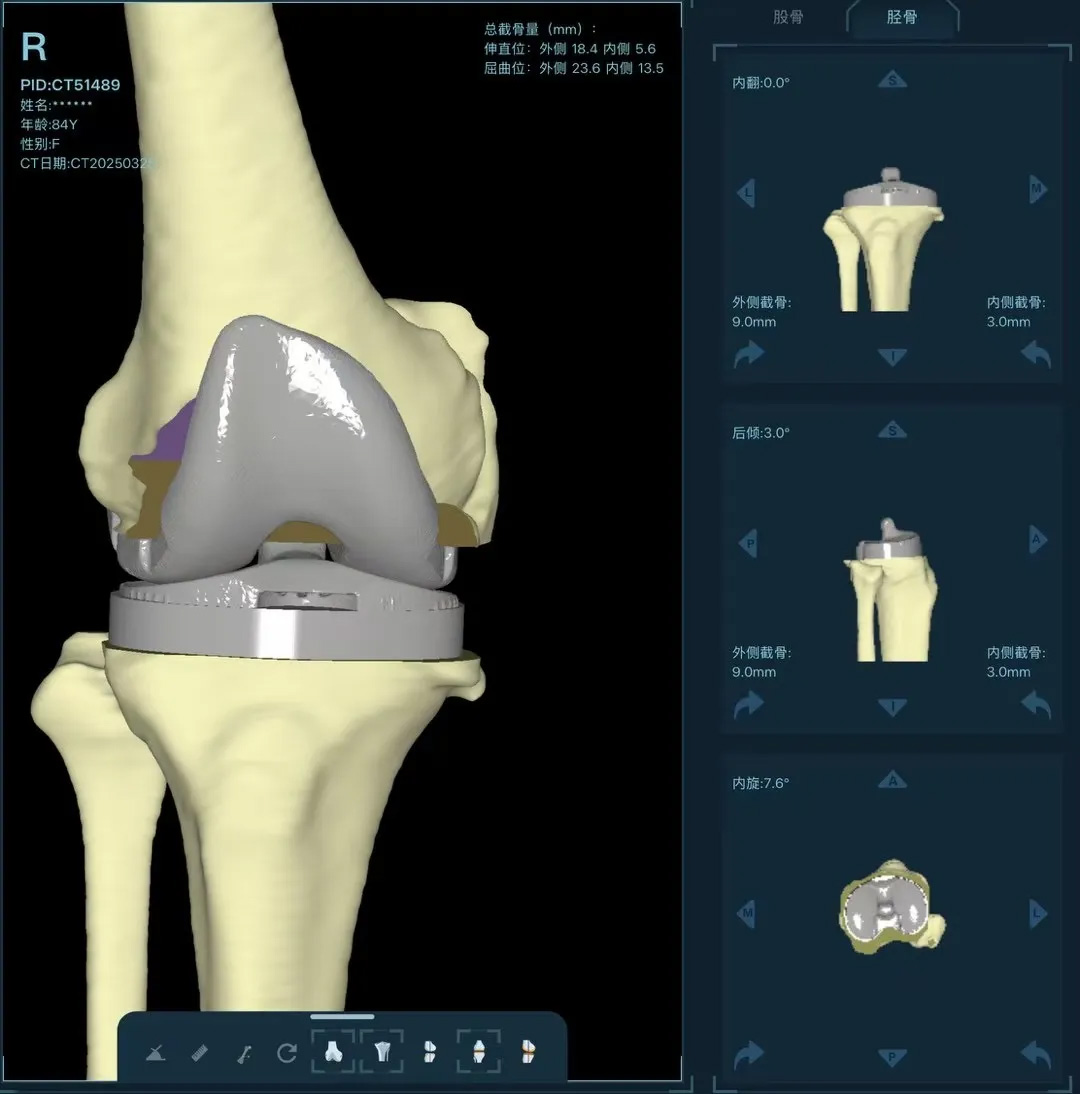

在家人幾乎放棄希望時,AI三維規(guī)劃技術(shù)為這場"關(guān)節(jié)保衛(wèi)戰(zhàn)"帶來轉(zhuǎn)機(jī)。

術(shù)前:AI通過CT掃描生成毫米級膝關(guān)節(jié)三維模型,為假體安裝設(shè)計出誤差小于1毫米的精準(zhǔn)方案 術(shù)中:智能導(dǎo)航系統(tǒng)如同"透視眼",引導(dǎo)醫(yī)生避開密集的神經(jīng)血管網(wǎng),截骨更精準(zhǔn),出血僅100ml 術(shù)后:當(dāng)天鄭阿婆即開始抬腿的康復(fù)訓(xùn)練,24小時內(nèi)扶助行器下地行走,三天后已能在病房走廊獨(dú)立行走,完成洗漱用餐 兩周后健步出院時,女兒含淚感慨“之前擔(dān)心她年紀(jì)大扛不住手術(shù),沒想到恢復(fù)這么快!現(xiàn)在每天散步比我還精神。知道技術(shù)這么先進(jìn),真該早點(diǎn)來!”

"這就像給傳統(tǒng)手術(shù)裝上了自動駕駛系統(tǒng)。"主刀醫(yī)生羅軍副院長用生動比喻解析技術(shù)突破。AI不僅實現(xiàn)假體“量身定制”,使用壽命可達(dá)20年以上,更通過三維路徑規(guī)劃將康復(fù)周期壓縮,實現(xiàn)術(shù)后24小時下地,2周回歸正常生活。同時,AI會避開重要組織,具有出血少、感染風(fēng)險低的特點(diǎn)。專家特別提醒,當(dāng)出現(xiàn)夜間持續(xù)性關(guān)節(jié)疼痛、步行能力低于10分鐘或關(guān)節(jié)畸形時,應(yīng)及時就醫(yī)評估,"別等到關(guān)節(jié)'報廢'才手術(shù)"。